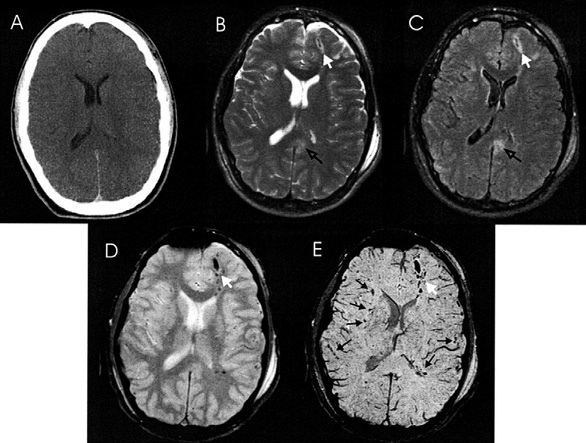

CMBs appear as small (2–10 mm in diameter), round or ovoid hypointense foci which exhibit blooming artifacts, thus making them more conspicuous on MRI sequences that are sensitive to susceptibility effects.

In clinical practice, the detection and number of CMBs can create uncertainty for clinicians, as they are also present in asymptomatic individuals, particularly the elderly. The reported prevalence of CMBs in older populations varies based on the average age of the group and the neuroimaging techniques used, with large population studies indicating a prevalence range of 5% to 35% in older adults [14–16]. Given this background prevalence, it becomes crucial to distinguish between traumatic and non-traumatic microbleeds when assessing older patients with a mild traumatic brain injury (mTBI). The most commonly observed types of CMBs are those associated with cerebral amyloid angiopathy (CAA) and hypertensive angiopathy. CAA-related microbleeds are typically lobar, often found in the parietal and occipital lobes, as well as cortical or subcortical areas. In contrast, hypertensive angiopathy is characterized by microbleeds predominantly located infratentorially, within the basal ganglia, thalamus, and periventricular white matter [17].

TMBs are detected in 27% of mild, 47% of moderate, and 58% of severe TBI cases. In contrast to microbleeds associated with small vessel disease or other non-traumatic conditions, traumatic CMBs exhibit distinct characteristics in terms of their location and appearance [17]. These trauma-induced lesions are frequently found in the corpus callosum and at the interface between the grey and white matter. Moreover, traumatic CMBs typically display a more radial and linear pattern, often aligning with the perivascular spaces. This configuration differs noticeably from the rounded shape commonly observed in CMBs linked to small vessel disease (SVD) [17]. These differences in distribution and morphology can aid in distinguishing traumatic from non-traumatic microbleeds in neuroimaging. However, absolute differentiation between these lesions remains challenging.